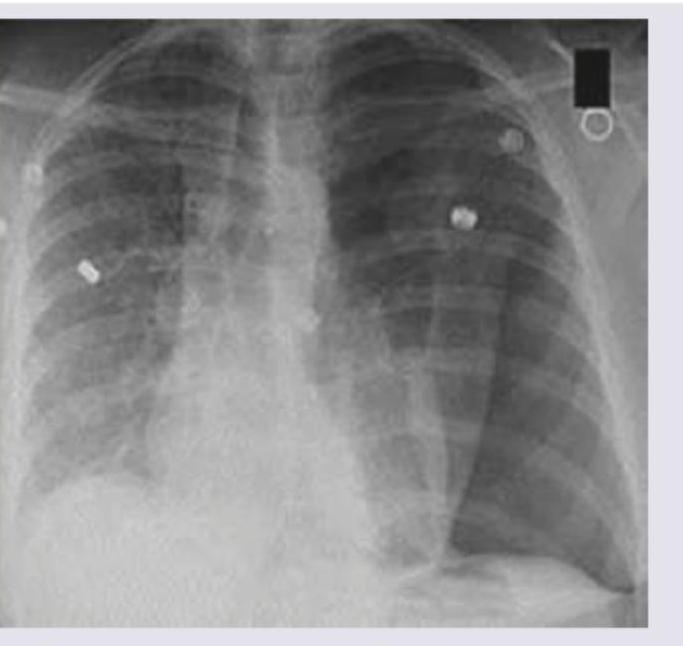

Question 7: A 1-year-old child with severe acute malnutrition develops pneumonia which is not responding to treatment. Chest X-ray picture is given. What is the likely etiology?

- C. Staphylococcus aureus (Correct Answer)

Explanation: ***Staphylococcus aureus*** - The chest X-ray shows extensive **bilateral infiltrates** with areas of potential **abscess formation** or **necrotizing pneumonia**, suggested by the poorly defined lucencies within consolidation, which are characteristic of Staphylococcal infection, especially in immunocompromised individuals like a malnourished child. - Staphylococcal pneumonia is often severe, can lead to **necrosis**, **cavitation**, and is known for its **resistance to common antibiotics**, explaining the poor response to initial treatment in a severely malnourished child. *Mycoplasma* - Mycoplasma pneumoniae typically causes **"walking pneumonia"** with milder symptoms and **diffuse interstitial infiltrates** visible on Chest X-ray, which are not as severe or focal as seen in the image. - It's less common to cause rapidly progressing, severe, and necrotizing pneumonia in this age group, even in malnourished children. *Pneumococcus* - **Streptococcus pneumoniae (Pneumococcus)** usually causes **lobar pneumonia** with dense, homogeneous consolidation in one lobe, often with a visible air bronchogram, rather than the more patchy, bilateral, and potentially necrotizing pattern seen here. - While it can be severe, especially in malnourished children, the radiographic pattern is less typical for pneumococcal infection. *Adenovirus* - Adenovirus can cause a range of respiratory infections, from common colds to severe pneumonia, especially in young children. However, the Chest X-ray findings typically include **perihilar infiltrates**, **bronchial wall thickening**, and hyperinflation, which do not fully match the extensive, severe, and potentially cavitating pattern observed. - While it can cause severe pneumonia, the given X-ray features, particularly the suggestion of necrosis, are less characteristic of adenoviral infection.